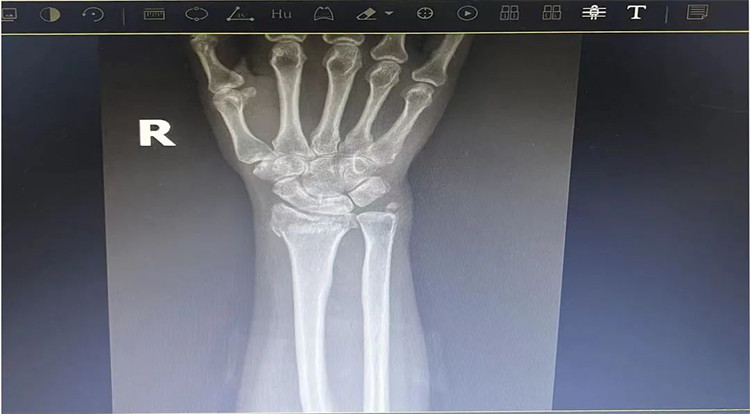

患者老年女性,50多歲,在騎電動車停下時因電動車倒下,右手著地,當即感覺,右腕及骶尾部腫痛伴右關節(jié)畸形、活動受限,急來我院就診。門診醫(yī)師結合病史、查體及輔助檢查后,診斷為:右橈尺骨遠端骨折、骶尾部挫傷并收入住院部。